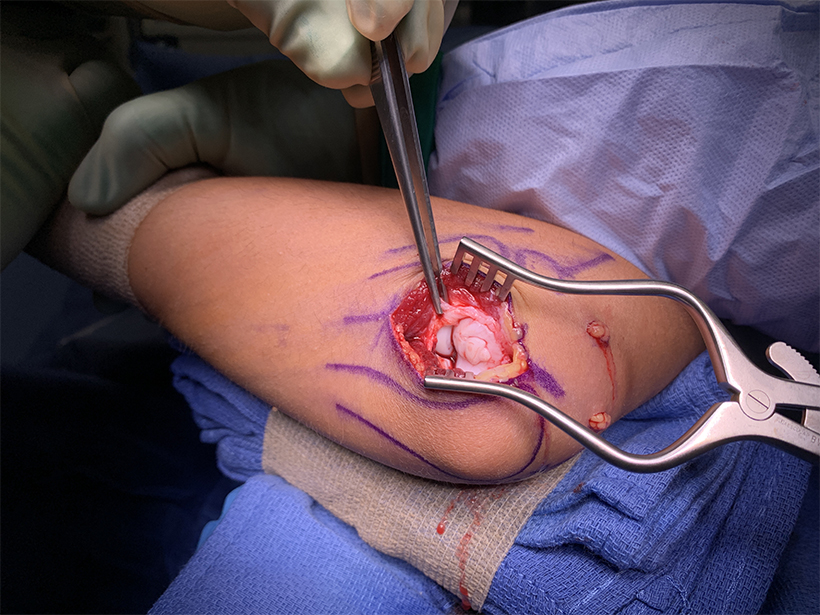

Fresh osteochondral allograft transplantation is a promising option for athletes with osteochondritis dissecans of the capitellum

Researchers from Kaiser Permanente found that fresh osteochondral allograft transplantation demonstrated favorable mid-term outcomes for the resurfacing of osteochondritis dissecans lesions of the humeral capitellum.